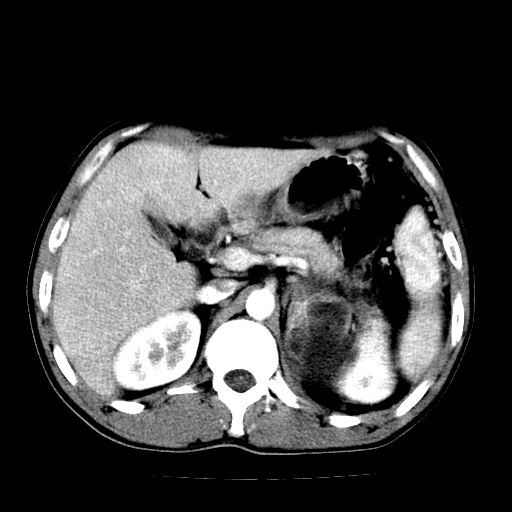

以下是引用天南地北在2007-4-30 13:36:00的发言:[br]支持慢性胰腺炎伴有假性囊肿

以下是引用andymaomao在2007-4-30 14:28:00的发言:[br]支持:1.慢性胰腺炎并假性囊肿形成可能;[br] 2.左肾形态稍增大,旋转不良。